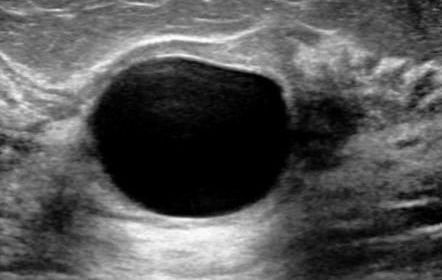

Advanced diagnostic procedures including imaging, biopsies, and genetic testing when needed. Our team collaborates to develop your personalized treatment plan.

- Advanced imaging & diagnostics

Breast Cancer Treatment

Comprehensive cancer care including diagnosis, surgical management, and multidisciplinary treatment plans with FRACS qualified surgeons.